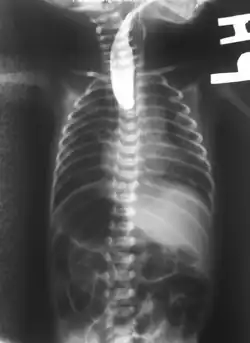

- une sonde « naso-gastrique » très fine peut être introduite dans l'œsophage du nouveau-né. Si elle est bloquée après quelques cm, c'est qu'il y a atrésie[3].

Dans presque tous les cas une anomalie de la trachée est associée, et dans la moitié des cas environ[3], l'atrésie de l'œsophage est associée à d'autres malformations, comme dans le cadre du syndrome de VATER (présent dans 10 % des cas[3]) ou de VACTERL. Il convient donc de rapidement rechercher activement d'autres malformations associées qui peuvent toucher le cœur (dans 30 % des cas), mais aussi le squelette (25 % des cas), les reins, les membres, le système digestif (25 % des cas) ou urinaire[3].... Une échographie et une radiographie de l'abdomen confirme le type d'atrésie et des examens complémentaires portent notamment sur le cœur (échocardiographie) et l'anus (une sonde recherche une éventuelle perforation)[3].